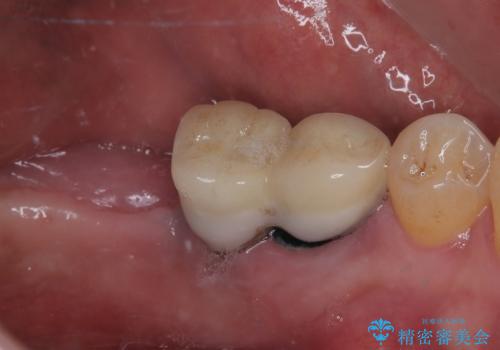

- 連結されている奥歯がグラグラしていて、インプラント治療を希望して来院された患者様です。

連結の手前の歯は歯根が破折して、クラウンが歯から外れており、奥の歯は動揺により歯根周辺の骨が吸収している状態でした。

骨吸収が甚大な後方は3ヶ月ほど待機して、手前は抜歯即時埋入により、短期間インプラント補綴治療を行うこととしました。